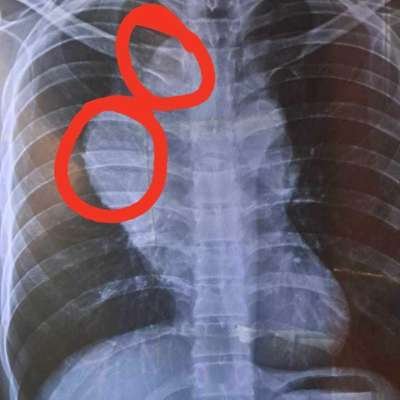

ভাই বিষয়টি কেউ এড়িয়ে যাবেন না আপনার একটু সহযোগিতায় বেঁচে যেতে পারে একটি প্রাণ। ছেলেটির নাম মোঃ আসাদুজ্জামান, ছেলেটি ডিপ্লোমা ইন টেক্সটাইল ইঞ্জিনিয়ার । ছেলেটির ক্যান্সার ধরা পড়েছে উন্নত চিকিৎসার জন্য তাকে দ্রুত দেশের বাইরে যেতে হবে। অনুগ্রহ করে একটু সহযোগিতার হাত বাড়িয়ে দিন, ছেলেটি অনেক অসহায় তার আর্থিক অবস্থা অনেক খারাপ । অনেক কষ্ট করে পড়াশোনা করেছে, সবেমাত্র চাকুরী শুরু করেছে এরই মধ্যে এই মরণব্যাধি তাকে ধরে ফেলেছে আপনাদের কাছে অনুরোধ রইলো সবাই যার যার সাধ্য মতো একটু সহযোগিতা করবেন।